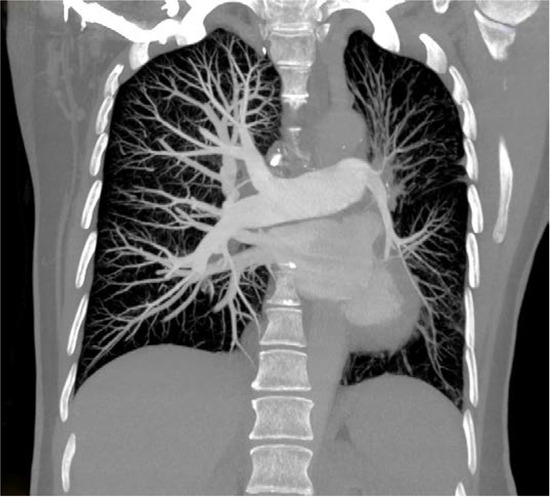

Thorax computed tomography (CT) revealed asymmetry with significantly smaller left lung. The left pulmonary artery immediately after separation was of extremely narrower lumen and so were lobar and segmental branches (Figure 2). Collaterals stemmed from mammary artery and bronchial artery (Figure 3). The results pointed towards UAPA. Subpleurally on the left, apically and basolaterally, scarred changes were noticed.

Incidence of hemoptysis increases with age in patients with UAPA. In the study where the median patient age was 14 years the incidence of hemoptysis was 20% while in another study where the median age was 40 years, the incidence of hemoptysis was more than 40% [7,9]. In the latter study of patients with UAPA, hemoptysis was the most common symptom [9]. It is considered that the presence of significant collaterals in older patients increases the possibility of hemoptysis. The most common collaterals stem from bronchial, phrenic, mammary, intercostal arteries, subclavian artery, subdiaphragmatic branches and coronary arteries [6,9]. Hemoptysis can be self-limiting or it can be massive with fatal outcome [7]. In case of our patient, collaterals stemmed from the mammary and bronchial artery.

Thorax CT reveals abnormal pulmonary artery that can be completely absent or finished 1 cm from its beginning or continuing in very narrow lumen, there can be preserved peripheral branches of the pulmonary artery, variable collateral circulation, possibly associated congenital anomalies, parenchymal changes such as mosaic attenuation and bronchiectasis due to recurrent infections [6,10].

Figure 3. Computed tomography (CT) showing marked volume loss in left hemithorax, narrow left pulmonary artery (arrowhead), collateral vessel, bronchial artery (arrow).